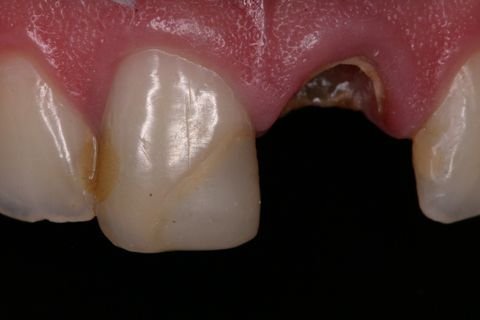

Aspecto Clínico Inicial

Aspecto clínico inicial (vista oclusal)

Paciente jovem do gênero masculino, apresentou-se à Clínica Integrada do Curso de Odontologia da Universidade Severino Sombra necessitando de um tratamento restaurador no dente 21. Ao exame clínico e radiográfico foi observado uma grande destruição coronária e tratamento endodontico satisfatório (Figuras 1, 2 e 3).